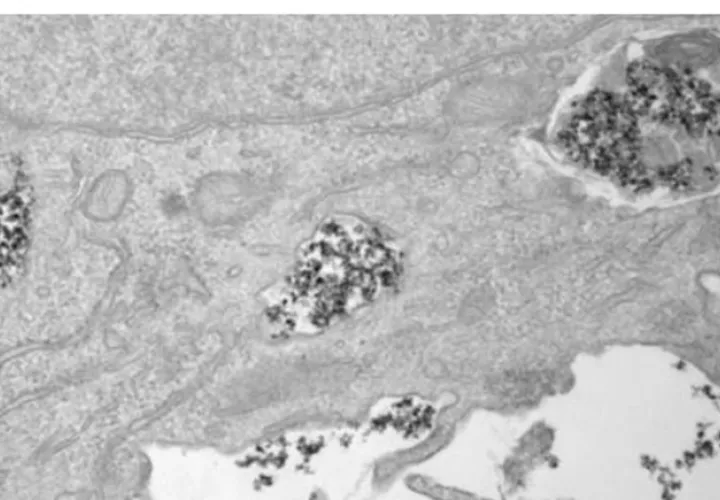

El estudio ha observado que en las células tumorales de modelos de ratón, las nanopartículas se acumulan en endolisosomas, donde se degradan más lentamente, mientras que en las células macrofágicas que envuelven al tumor, la degradación tiene lugar con más o menos rapidez, según sea el recubrimiento.